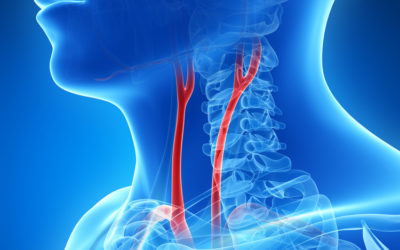

10.4172/lpma.1000115Risk Factors of Admission Delay after Ischemic Stroke in an Urban Tertiary Care Setting in China